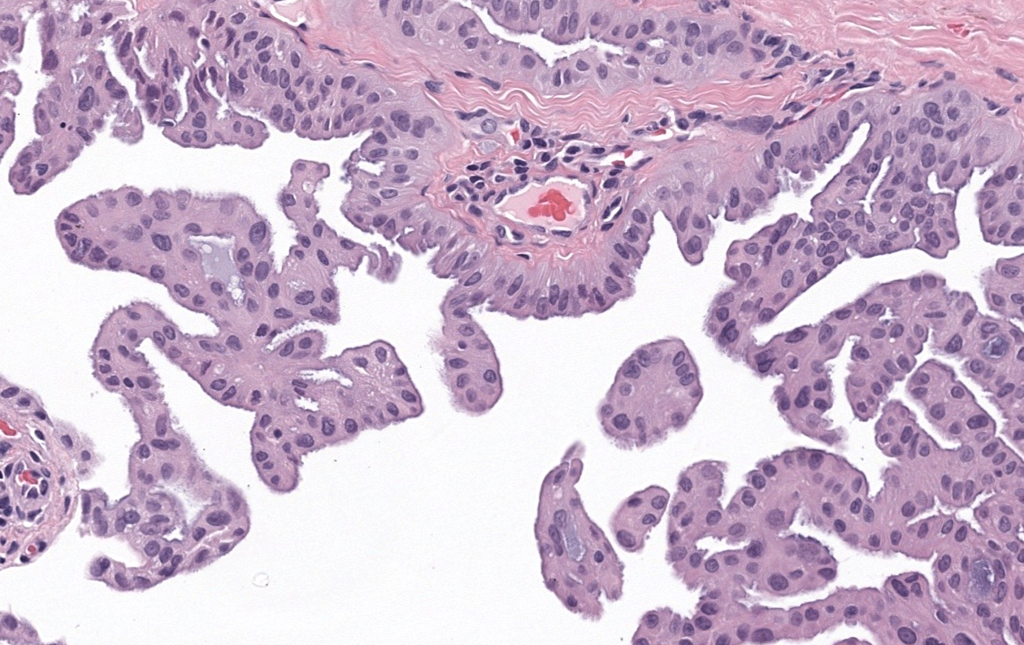

Nombres alternativos: quiste sudoríparo; quiste de glándulas de Moll (apocrino); “tipo Robinson” (múltiple eccrino).

Primera descripción: múltiples hidrocistomas eccrinos descritos por Robinson (1893); el apocrino (cystadenoma/hidrocistoma) delineado por Smith & Chernosky (1974).

Asociaciones sindrómicas (red flag): múltiples apocrinos perioculares pueden ser marcador de síndrome de Schöpf–Schulz–Passarge (SSPS) (ectodermatosis) y, más raramente, de formas relacionadas con Goltz-Gorlin.